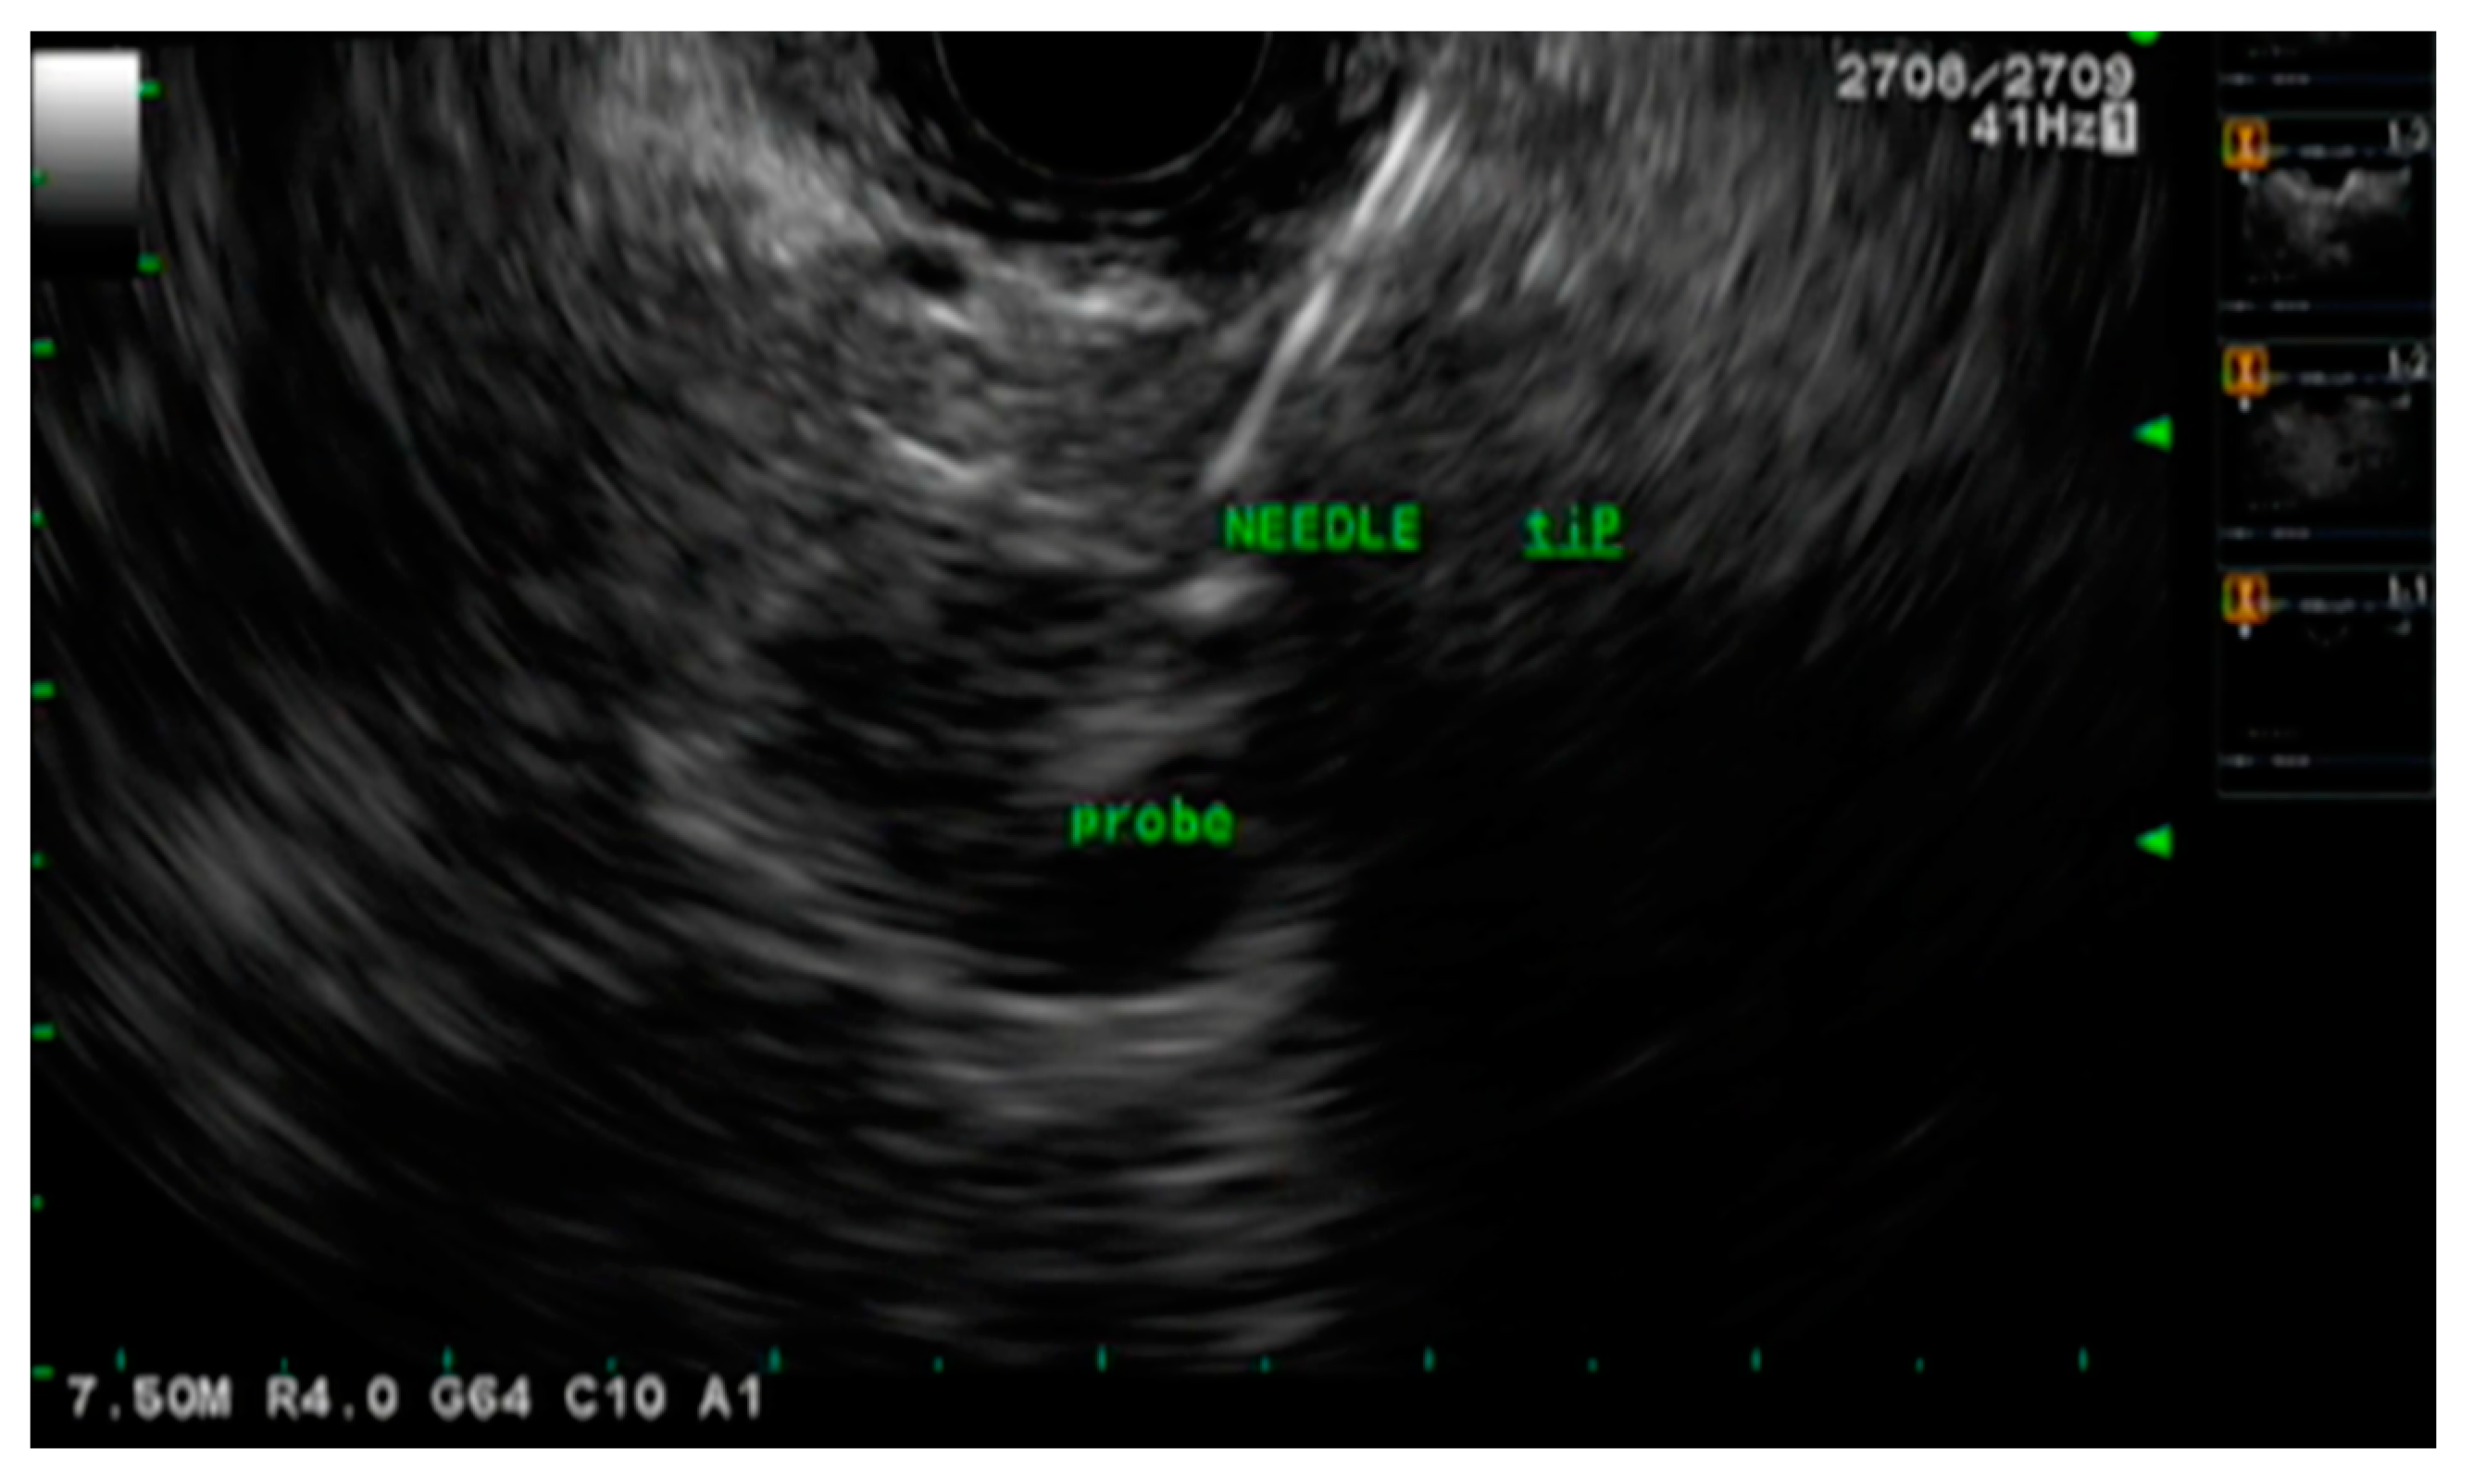

- Pishvaian, A.C.; Collins, B.; Gagnon, G.; Ahlawat, S.; Haddad, N.G. EUS-guided fiducial placement for CyberKnife radiotherapy of mediastinal and abdominal malignancies. Gastrointest. Endosc. 2006, 64, 412–417. [Google Scholar] [CrossRef]

- Ammar, T.; Coté, G.A.; Creach, K.M.; Kohlmeier, C.; Parikh, P.J.; Azar, R.R. Fiducial placement for stereotactic radiation by using EUS: Feasibility when using a marker compatible with a standard 22-gauge needle. Gastrointest. Endosc. 2010, 71, 630–633. [Google Scholar] [CrossRef]

- DiMaio, C.J.; Nagula, S.; Goodman, K.A.; Ho, A.Y.; Markowitz, A.J.; Schattner, M.A.; Gerdes, H. EUS-guided fiducial placement for image-guided radiation therapy in GI malignancies by using a 22-gauge needle (with videos). Gastrointest Endosc. 2010, 71, 1204–1210. [Google Scholar] [CrossRef] [PubMed]

- Park, W.G.; Yan, B.M.; Schellenberg, D.; Kim, J.; Chang, D.T.; Koong, A.; Patalano, C.; Van Dam, J. EUS-guided gold fiducial insertion for image-guided radiation therapy of pancreatic cancer: 50 successful cases without fluoroscopy. Gastrointest. Endosc. 2010, 71, 513–518. [Google Scholar] [CrossRef]

- Sanders, M.K.; Moser, A.J.; Khalid, A.; Fasanella, K.E.; Zeh, H.J.; Burton, S.; McGrath, K. EUS-guided fiducial placement for stereotactic body radiotherapy in locally advanced and recurrent pancreatic cancer. Gastrointest. Endosc. 2010, 71, 1178–1184. [Google Scholar] [CrossRef]

- Varadarajulu, S.; Trevino, J.M.; Shen, S.; Jacob, R. The use of endoscopic ultrasound-guided gold markers in image-guided radiation therapy of pancreatic cancers: A case series. Endoscopy 2010, 42, 423–425. [Google Scholar] [CrossRef]

- Choi, J.-H.; Seo, D.-W.; Park, D.H.; Lee, S.K.; Kim, M.-H. Fiducial Placement for Stereotactic Body Radiation Therapy under Only Endoscopic Ultrasonography Guidance in Pancreatic and Hepatic Malignancy: Practical Feasibility and Safety. Gut Liver 2014, 8, 88–93. [Google Scholar] [CrossRef] [PubMed]

- Dávila Fajardo, R.; Lekkerkerker, S.J.; van der Horst, A.; Lens, E.; Bergman, J.J.; Fockens, P.; Bel, A.; van Hooft, J.E. EUS-guided fiducial markers placement with a 22-gauge needle for image-guided radiation therapy in pancreatic cancer. Gastrointest Endosc. 2014, 79, 851–855. [Google Scholar] [CrossRef] [PubMed]

- Dhadham, G.C.; Hoffe, S.; Harris, C.L.; Klapman, J.B. Endoscopic ultrasound-guided fiducial marker placement for im-age-guided radiation therapy without fluoroscopy: Safety and technical feasibility. Endosc. Int. Open 2016, 4, E378–E382. [Google Scholar] [PubMed]

- Tabernero, S.; Prados, S.; Rubio, M.D.C.; de la Morena, F.; López, M.; Sánchez, E. Endoscopic ultrasound-guided fiducial placement in pancreatic tumors: Safety and technical feasibility. Rev. Esp. Enferm. Dig. 2019, 111, 425–430. [Google Scholar] [CrossRef]